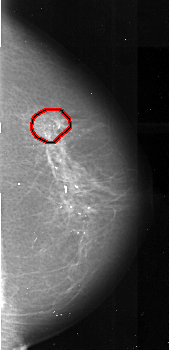

A_1021_1.RIGHT_MLO

A_1021_1.RIGHT_CC

RIGHT_CC LINES 5236 PIXELS_PER_LINE 2521 BITS_PER_PIXEL 16 RESOLUTION 42 OVERLAY

RIGHT_MLO LINES 5491 PIXELS_PER_LINE 2491 BITS_PER_PIXEL 16 RESOLUTION 42 OVERLAY

FILE: A_1021_1.RIGHT_MLO.OVERLAY

TOTAL_ABNORMALITIES 1

ABNORMALITY 1

LESION_TYPE MASS SHAPE ARCHITECTURAL_DISTORTION MARGINS SPICULATED

ASSESSMENT 4

SUBTLETY 3

PATHOLOGY MALIGNANT

TOTAL_OUTLINES 1

BOUNDARY